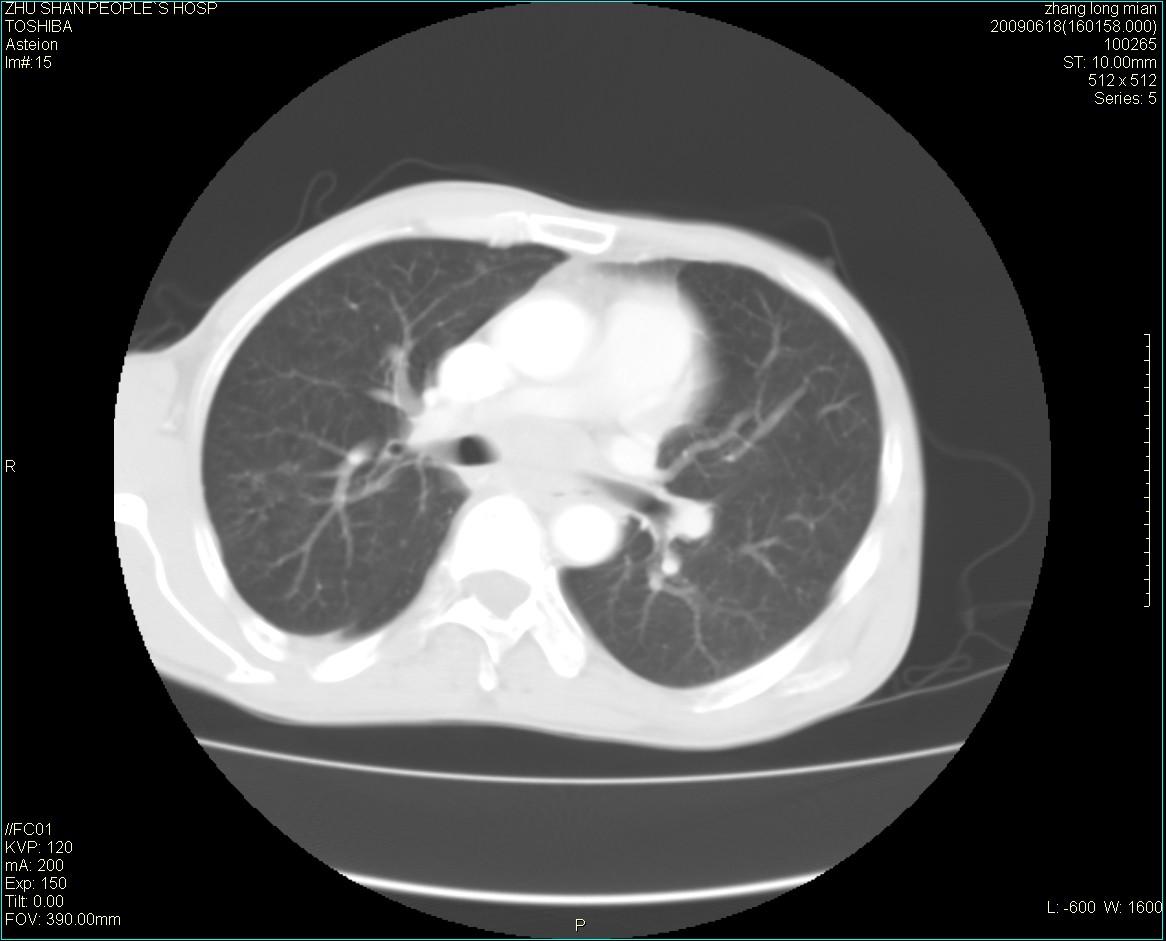

男性 65岁 胸片发现右下肺包块.诊断肺ca并纵隔转移没有问题吧!

两侧胸廓不对称,右侧呈塌陷改变,右肺萎缩。

右下肺见浅分叶状软组织块影,边缘有毛刺,其下部似见不完整偏心空洞影,邻近胸膜凹陷征,并胸腔积液。

增强见纵隔区气管隆突上下及左肺门区肿大淋巴结。左肺感染性病灶。

另见右上肺见一枚小结节影,性质待定。